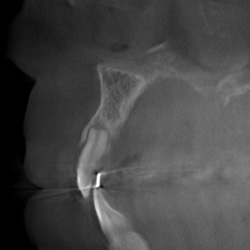

• Knöcherne Erkrankungen des Kiefergelenks

• Ausschluss primärer Kiefergelenkerkrankungen

Präimplantäre Diagnostik OberkieferSinusbogenaugmentationKiefergelenk